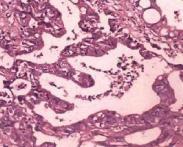

肝外膽管損傷

• 肝外膽管損傷

628健康網為您分享有關肝外膽管損傷的癥狀,肝外膽管損傷的治療方法,肝外膽管損傷的預防知識,肝外膽管損傷的癥狀圖片,肝...